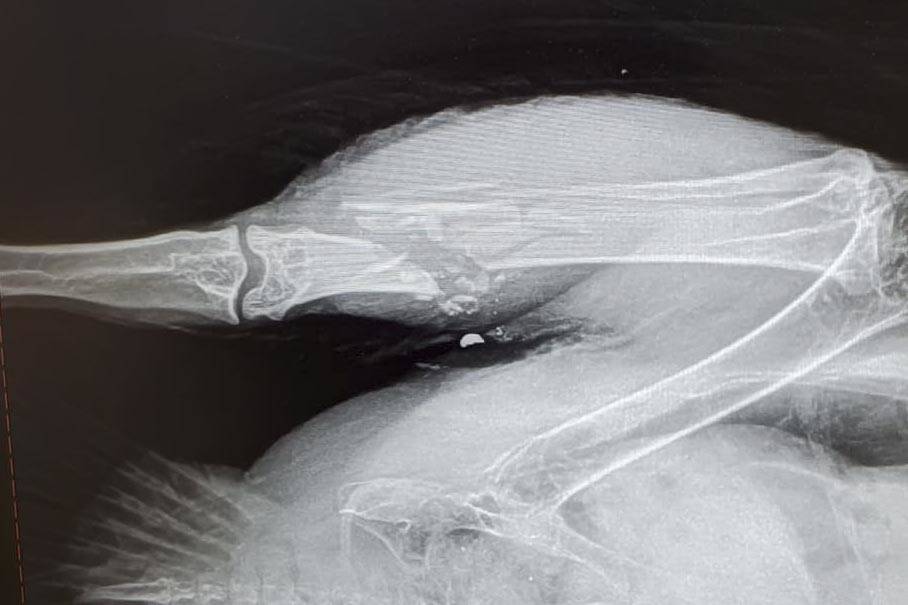

For the eagle rescued near Montana Creek Road on Dec. 22, its rescuers weren’t even aware it was such a case until the Alaska Raptor Center in Sitka X-rayed the bird, and passed word that it had been shot, Benner said. The bird, whose pelvis was shattered and had mounting lead poisoning from the lead shot (shotgun ammunition) that is illegal in Alaska, had to be euthanized, Benner said.

Lady Baltimore was another such bird, but her story has a happier ending. Found in Douglas in 2006 and rescued by the JRC, she had taken a round damaging her beak and wing.

“Apparently she was shot in the beak and the rest of the right wing. I think it was a bullet as opposed to shot, but she had been out in the wild for two weeks after she had been shot,” Benner said. “She was shot in the wing, so she couldn’t fly. The impact of the bullet also caused a detached retina in her left eye.”